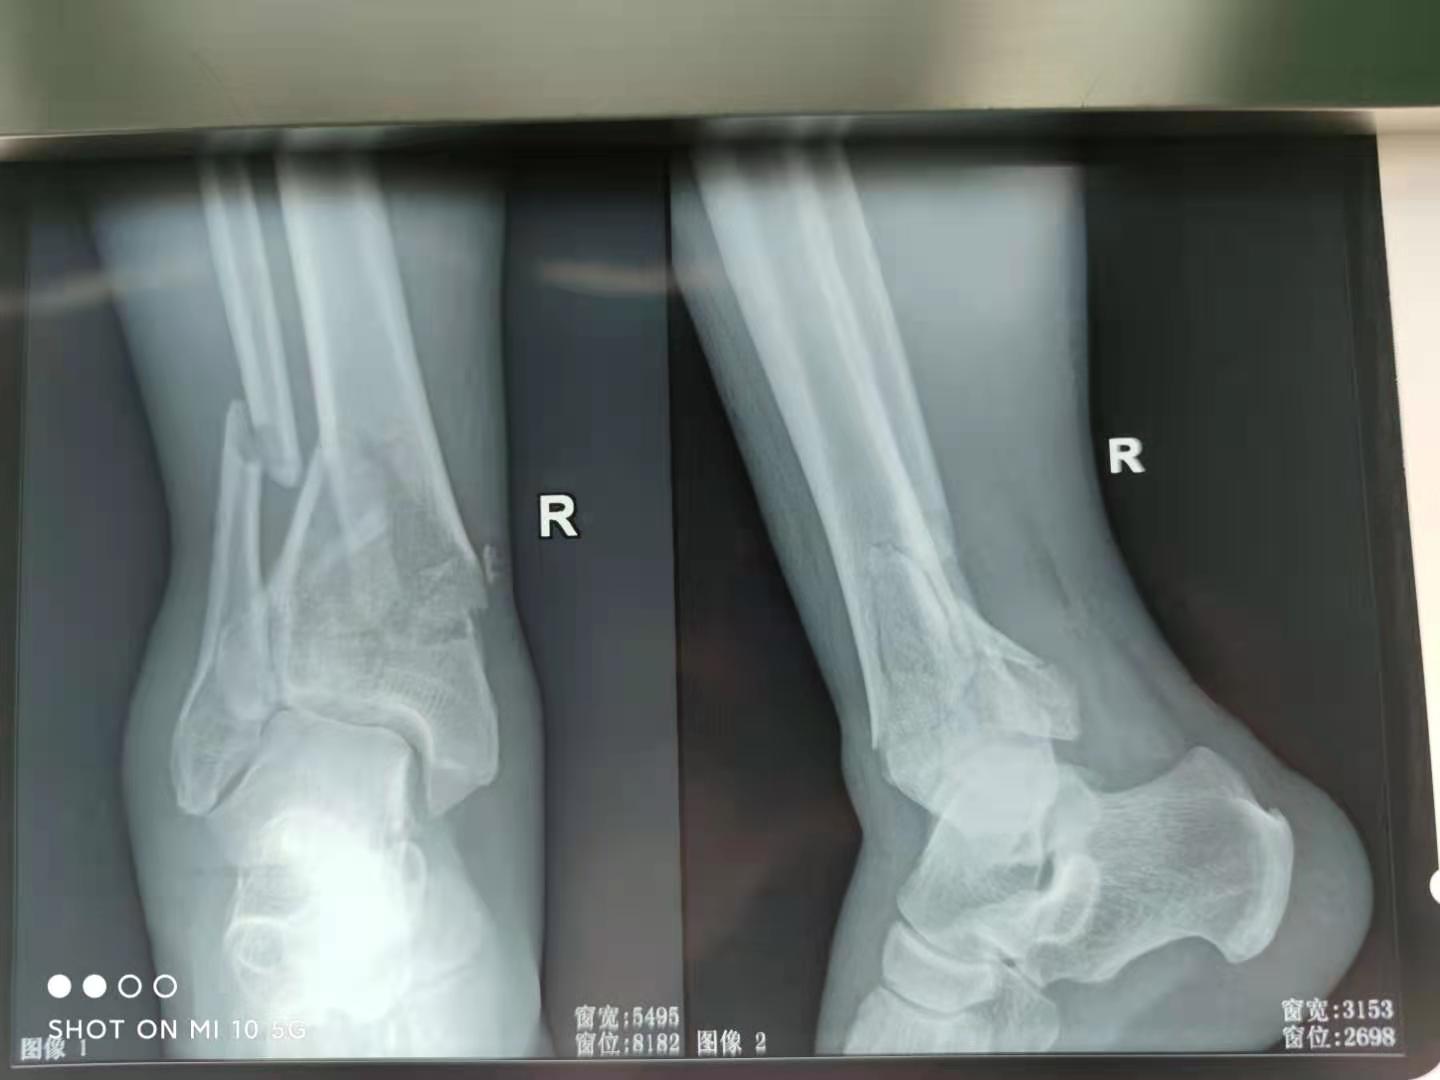

首先,踝关节的X线片是必须的,多数踝关节扭伤后,如果发生骨折,X线片大多可以明确。

踝关节骨折X线片

当然,如果X线片无法明确骨折类型和损伤机制,CT检查就显得相对好了,尤其是CT在确定Pilon骨折变异的踝关节骨折方面以及下胫腓联合以下的骨折明确胫骨关节面的压缩情况等方面很有优势。